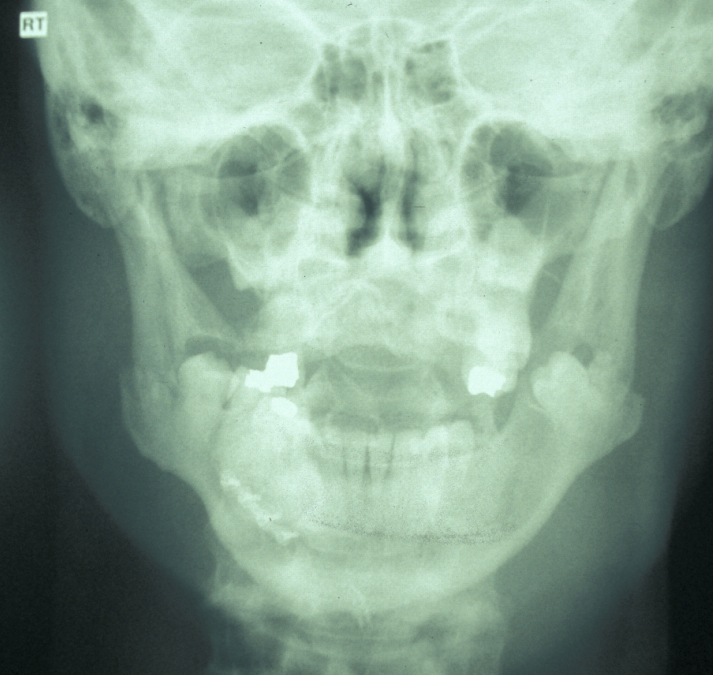

The combination of plain X-ray radiographs taken from different directions gives adequate diagnostic information for most mandibular fractures (DPT, dental panoramic tomogram (see Figure 2) and posteroanterior radiographs (see Figure 3)).

Figure 3: Posteroanterior radiograph of bilateral mandibular angle fractures. Same case as in Figure 2.

If the patient is unable to stand in the DPT machine, left and right lateral oblique mandibular views will give good imaging of the body of the mandible.  If the patient has multiple complex maxillofacial fractures a CT scan (CT coronal and axial images, with or without 3D reformatting) is helpful (see Figure 4). The CT scan will help assess condylar fracture position, angulation and any fractured dislocation of the condylar head. A CT scan is also useful to image multi-part mandibular body fractures.